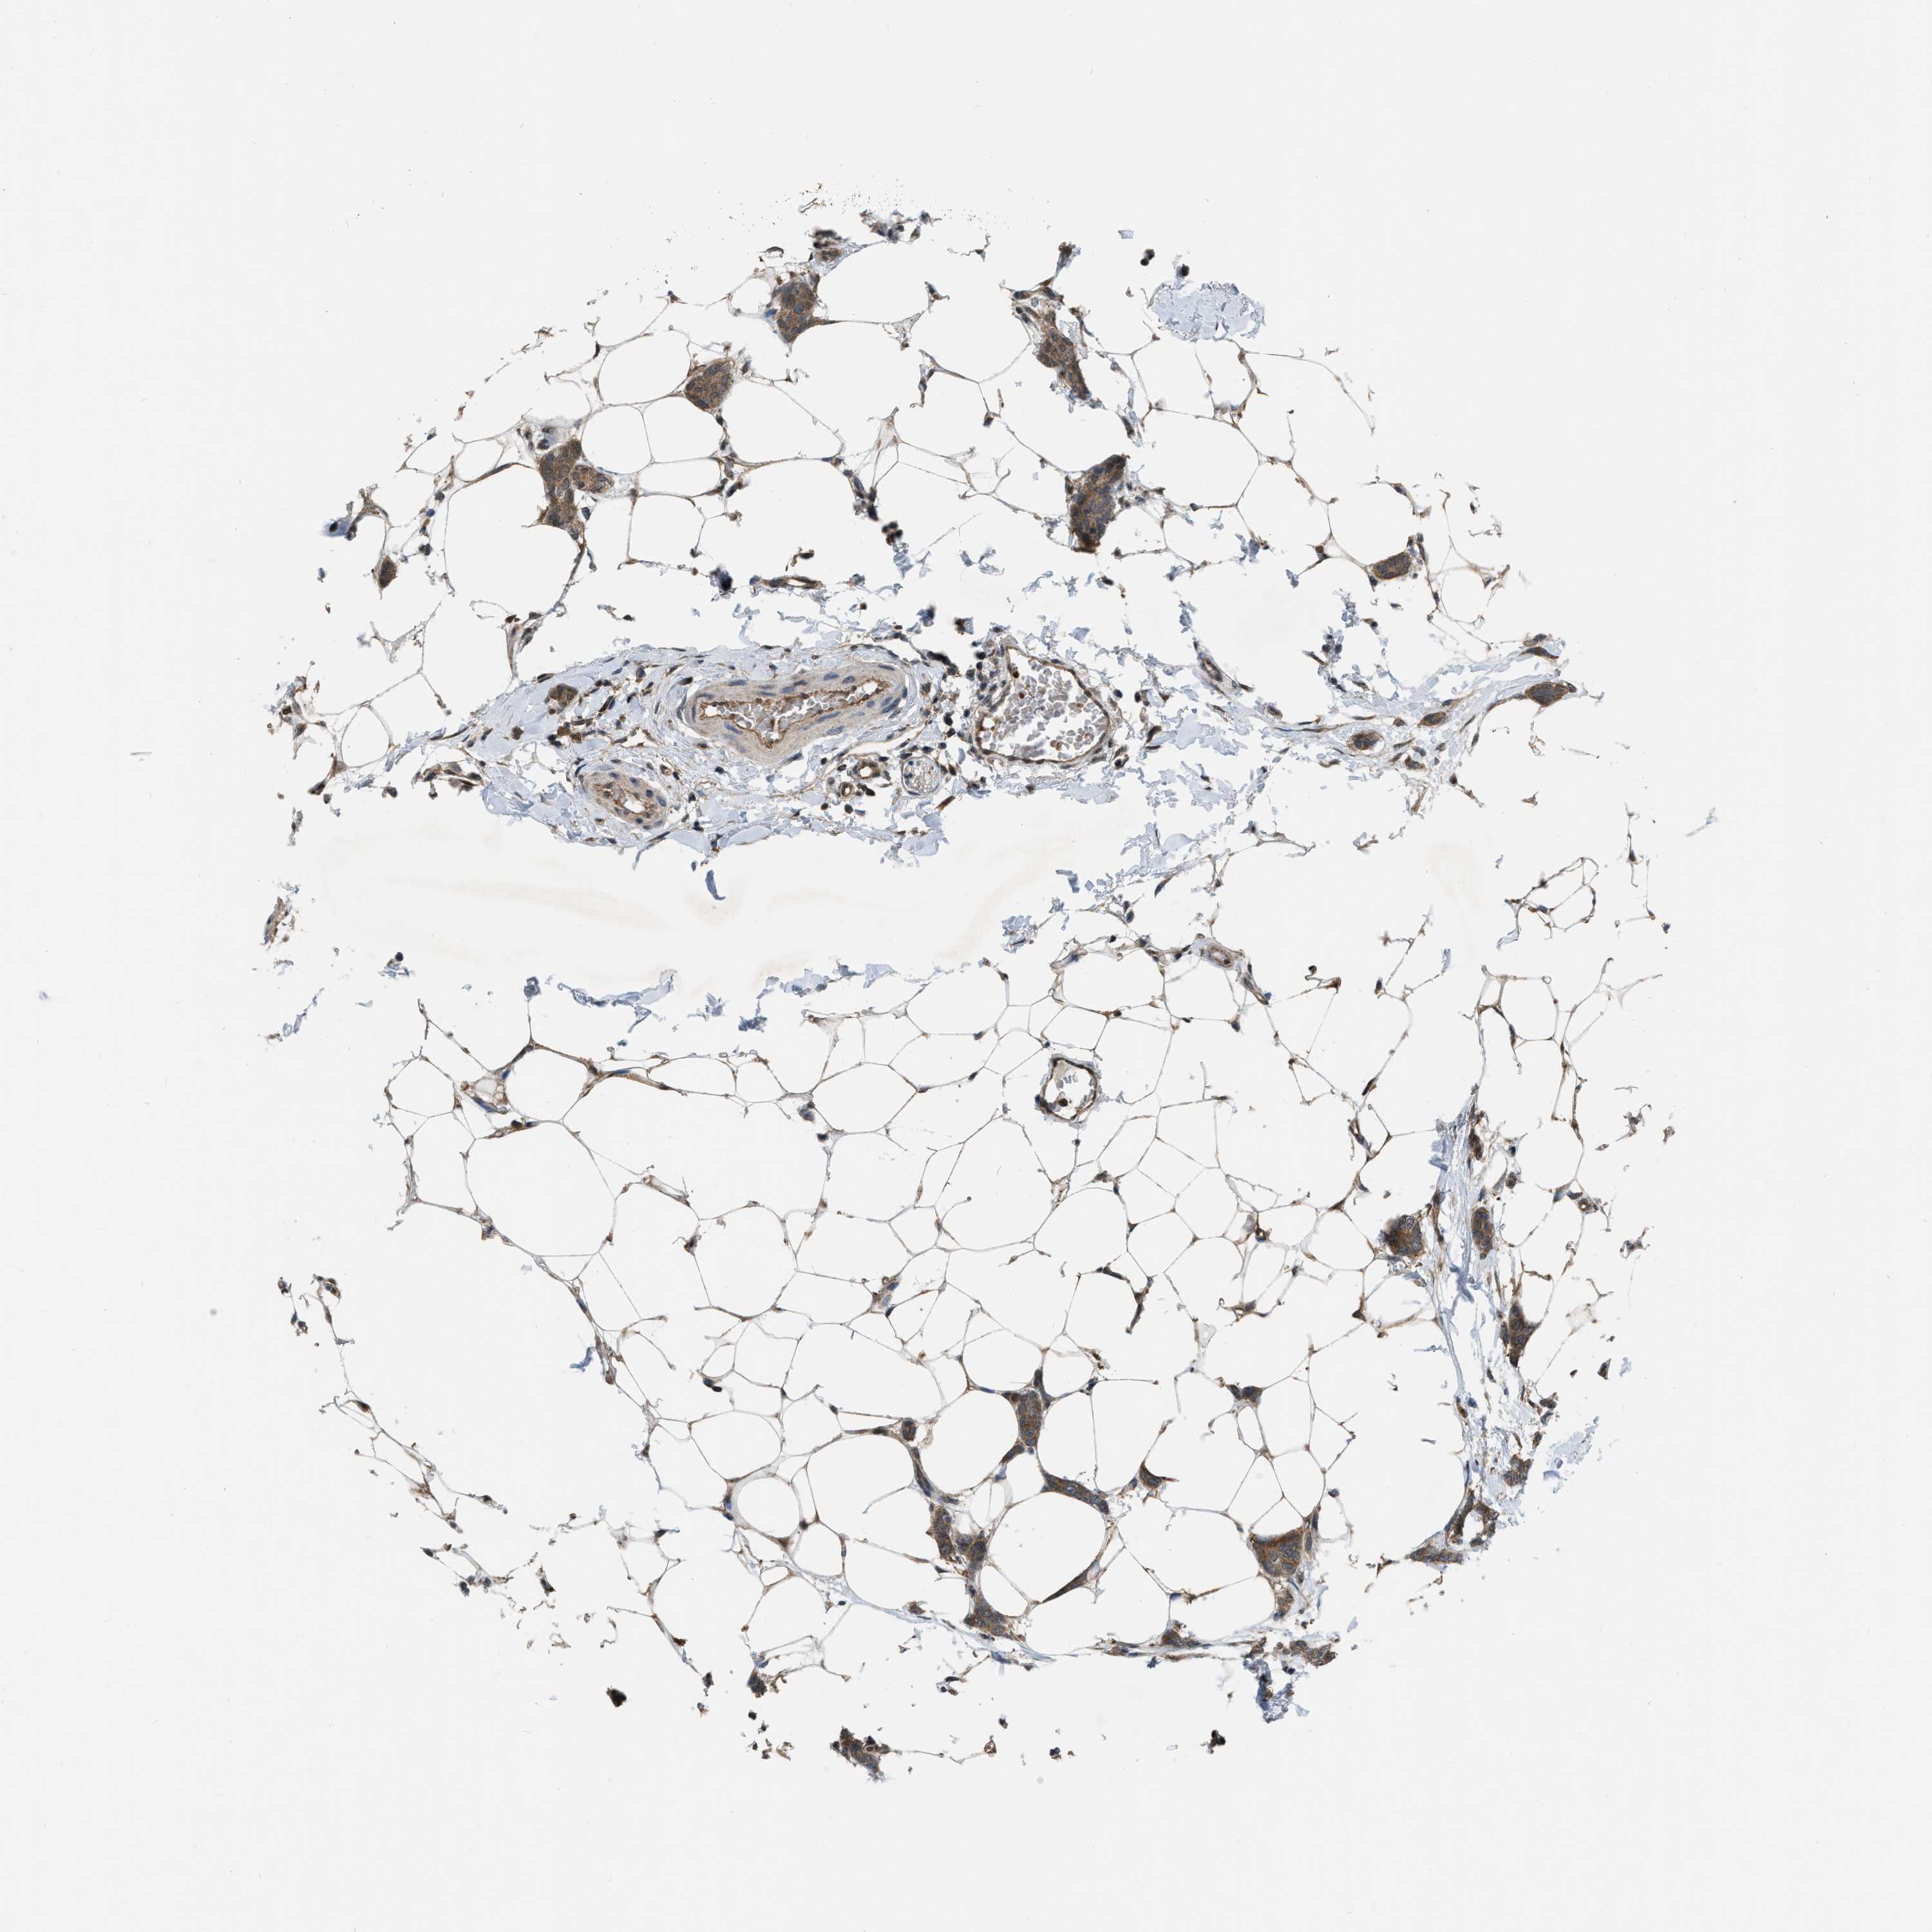

CANCER BREAST CANCER Show tissue menu

BRCA TCGA BRCA VALIDATION PROTEIN EXPRESSION